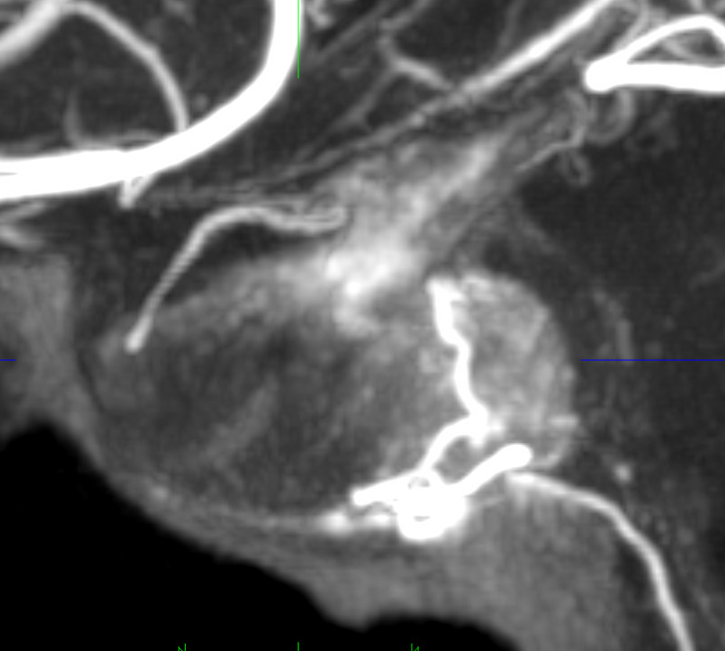

Sagittal MIP of the pituitary

DSA — yes, they do exist on DSA also. A slight contralateral oblique is probably best — to throw them off other vessels. Here, an LAO of right ICA injection shows a farily promenent superior hypophyseal (white arrow, with an infundibulum), supplying the pituitary stalk (black arrwos). Also seen is inferior hypophyseal (dashed white arrow) supply of the posterior pituitary (dashed black arrow)